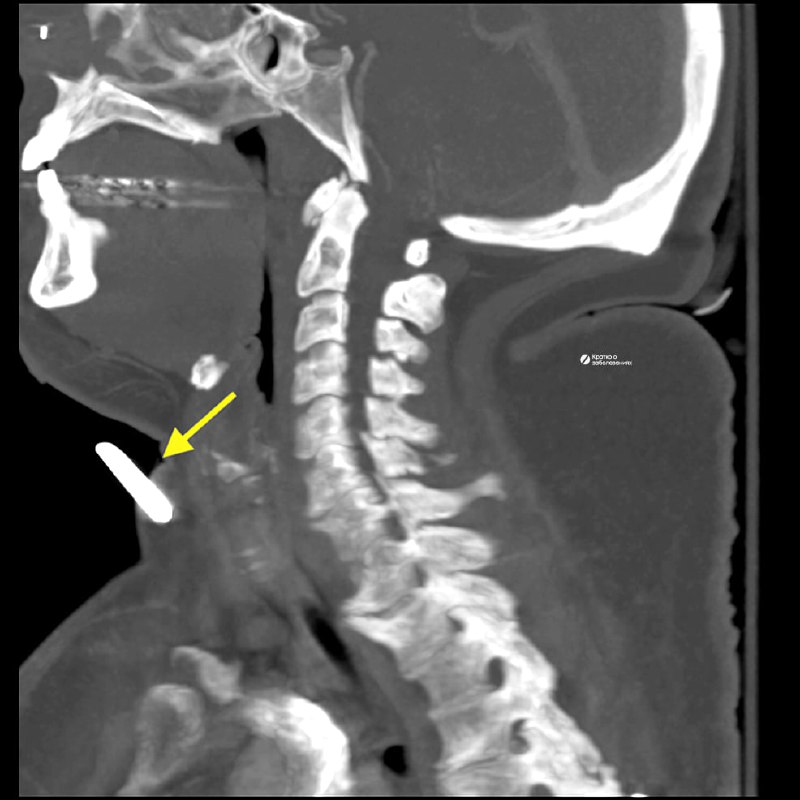

Удаление инородного тела правой орбиты:

5 мар. 2026 г.

1.8k 11 8